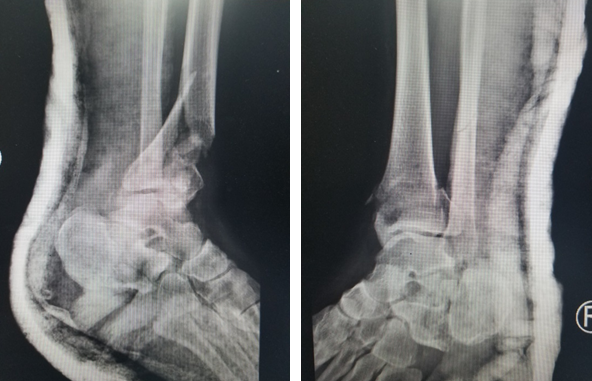

在必威官方首页官网betway,急诊医生给华大姐完善各项检查,发现她的伤情很严重:双pilon骨折,双跟骨骨折,腰椎多发骨折。急诊医生立刻联系足踝科徐明亮主任前来会诊,徐主任仔细检查了华大姐的病情,安排她先进行距骨牵引,消肿一周,等待合适的手术时机。

术前

“病人双侧跟骨粉碎性骨折,胫骨远端粉碎性骨折,受伤暴力大,周围软组织损伤也比较重,短时间内局部出现张力性水泡,早期切开后,一是容易导致伤口难以缝合,另外也增加了感染的机会,所以要在消肿以后,再给她切开复位内固定,减少患者伤口感染的几率。”徐明亮主任说。